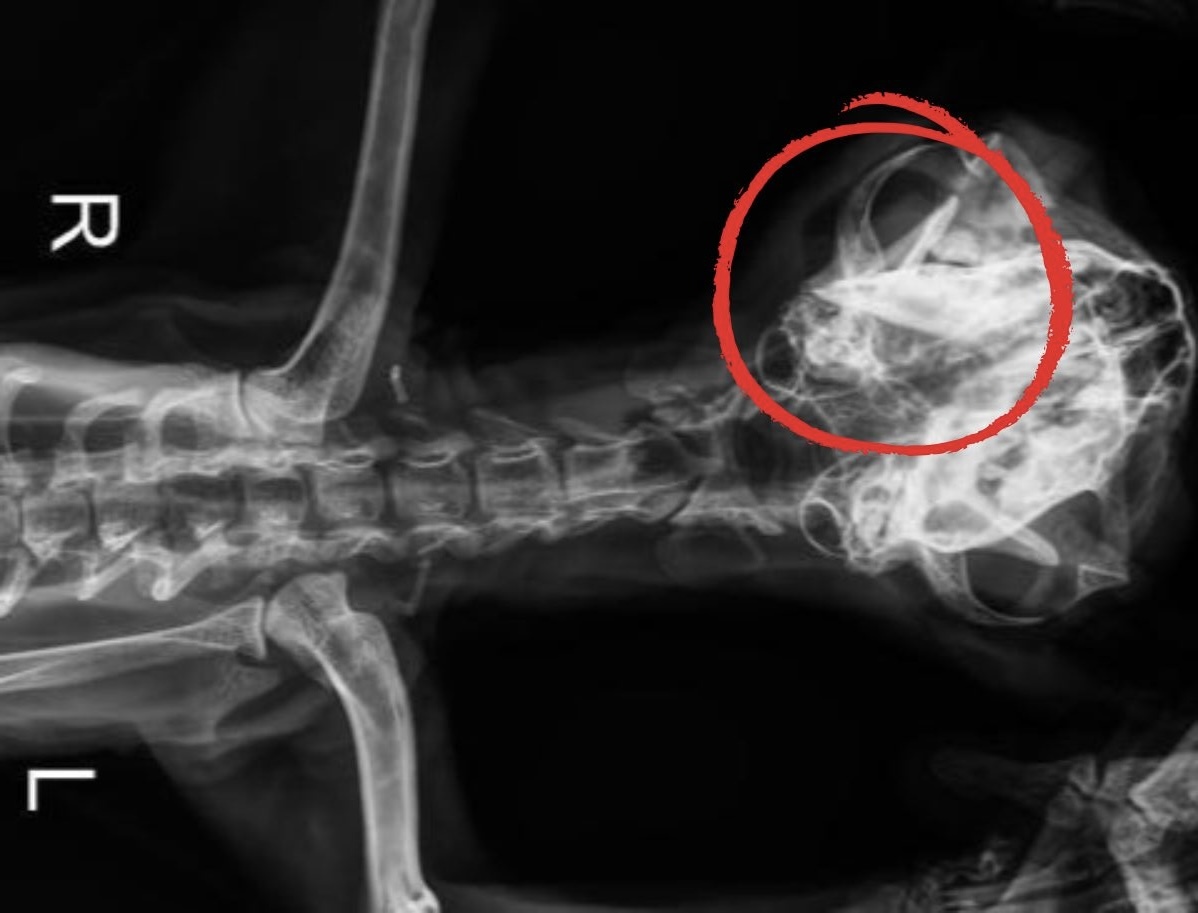

W klinice doktor od razu powiedziała, że poznaje Arielkę. Bywała tu na wizytach wcześniej, kiedy jeszcze była kochanym domowym kotkiem… Doktor była wstrząśnięta, kiedy zobaczył w jakim stanie jest Arielka. Podała jej od razu leki na wzmocnienie i przeciwbólowe oraz kroplówkę. Kiedy leki zaczęły działać, zrobiła jej RTG. A potem pokazała mi na zdjęciu miejsce, gdzie widać że szczęka kotki jest poważnie uszkodzona w wyniku jakiegoś mechanicznego urazu. Dlatego Arielka nie jest w stanie sama jeść ani nawet utrzymać jedzenia w pyszczku. Doktor mówi, że nie da się pomóc jej inaczej, niż przez operację. Trzeba pod narkozą przeprowadzić rekonstrukcję szczęki. Do czasu operacji koteczka musi być karmiona dożylnie.